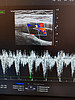

Так, одна из пациенток поликлиники №2 на протяжении многих лет наблюдалась у кардиолога из-за гипертонической болезни, ожирения и сахарного диабета 2 типа. Ей была успешно проведена радиочастотная абляция рецидивирующей формы фибрилляций предсердий. Через какое-то время у женщины появились новые симптомы – варикозное расширение вен и боли в правой голени. Врач-хирург направил пациентку на допплеровское исследование артерий и вен нижних конечностей.

Ирина Ковальчук сумела выявить причину неприятных симптомов. Оказалось, что у женщины образовалась артерио-венозная фистула – аномальное соединение между артерией и веной, которое нарушает кровообращение, может привести к образованию тромбов и сердечной недостаточности.

– Благодаря своевременному выявлению фистулы пациентка была направлена к ангиохирургу. Диагноз был подтвержден, назначено лечение, – подчеркнула заведующая отделением функциональной и ультразвуковой диагностики. – Пациентка находится на диспансерном наблюдении и чувствует себя удовлетворительно. Врачи отмечают положительную динамику: размеры артерио-венозной фистулы уменьшились, что улучшило прогноз заболевания.